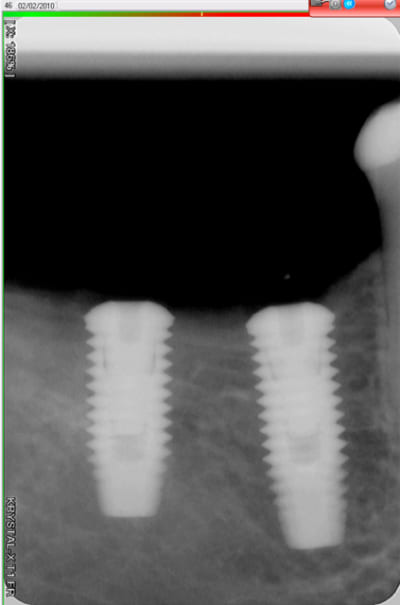

Voici trois Rx : cratère ou pas ? quel taux d'échec à 5 ans (tout les implants), ce sont les mêmes : 3I plateforme plate, deux temps chir, pas de plateform switching, pilier vissé prothèse scellée, 3 mois d'OI.

Crat 1 k8pnfh - Eugenol

Crat 2 ra8vyw - Eugenol

Crat 3 hpsffn - Eugenol

j'ai posé deux easy avec le biseau enfoui dans l'os. A 3 mois, pose des piliers de cicatrisation et un mois plus tard pose de la prothèse.

manifestement l'os ne reste pas en place à ce niveau

je prendrai un cliché dans 3 mois pour évaluer ce qu'il advient de la zone mésiale du col de l'implant distal.

46 47 xvjblf - Eugenol

46 47 pose kiaay7 - Eugenol